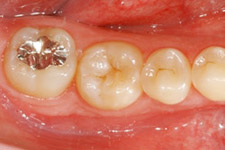

4年後

移植後4年。親知らずが第一大臼歯の代わりを担っています。

4年後。移植後に根が少し成長しているのが分かります。歯の神経もつながっています。